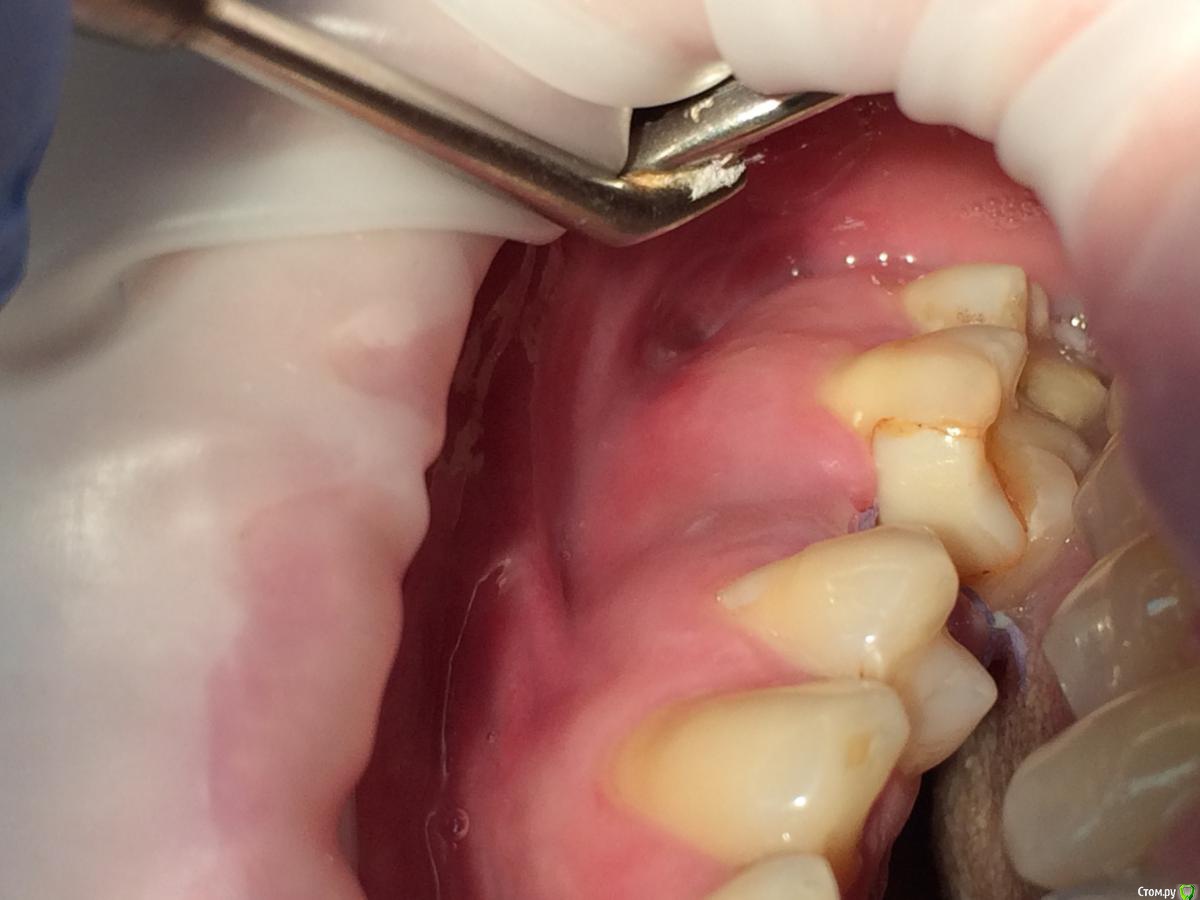

Graffwoman Опубликовано 25 февраля, 2018 Поделиться Опубликовано 25 февраля, 2018 Здравствуйте,уважаемые коллеги! Помогите кто-чем может)). Надо - очень срочно....(((8 дней назад установлен имплантат Osstem. Жалобы на сохраняющуюся одинаковую со дня вмешательства тупую,неприятную,ноющую боль в области проекции верхушки имплантата. Появляется примерно через 3 часа после пробуждения. Ротовые ванночки мирамистином и пьет нимесил 2 раза в сутки.Температура-36,4 *. Перед установкой хирург заметил небольшую полоску гноя из кармашка 26 (а,может,размягченые остатки пищи из под нависающего края пломбы 26,он был расположен под десной ,но похоже ,что гной). Операцию по установке откладывать не стали,пациент пополоскал рот и бетадином было обработано операционное поле.Четко понимаю,что отошли от протокола : не назначили антибиотикотерапию и осмотр на 3-й день произведен не был-так получилось..В анамнезе 3 года назад -двусторонний гайморит.Сейчас выделения из носа прозрачные только утром незначительное количество-то справа ,то слева. Когда появились не очень помнит,возможно до имплантации Антибиотики начал пить на 5- сутки после операции. При осмотре на 8-й день пальпация щеки и слизистой по своду переходной складки болезненна в одной точке чуть дистальнее проекции верхушки имплантата..Шов не состоятелен. В ране гнилостный запах .Обработали рану,хлоргексидином.На прицельном -пока спокойно.Это воспаление в мягких тканях без резорбции в периимплантной области ?Надо удалить имплантат , пока не поздно?Надежды никакой ? Посоветуйте,что делать,пожалуйста .С благодарностью надеюсь на ответ. Ссылка на комментарий

rytovst Опубликовано 25 февраля, 2018 Поделиться Опубликовано 25 февраля, 2018 внесу свою лепту Сосудосуживающий капли в нос на 10 дней - в каждый носовой ход Амоксиклав 1000 мг по 1 2 рд 5 дней либо супракс либо таваник - их легче принимать Бифиформ АциполНимесил 100 мг по 1 пакет 2 рд 7 дней Хлоргексидин или мирамистин - ротовые ванночки до 6 раз в день, потом сразу солкосерил дентальный наносить - он держится намного лучше других гелей и паст ,хватает трех раз в день Ну ,вообщем, это стандартный набор Из протокола хотел выяснить 1. чем сверлились ? был ли использован набор для закрытого синуса ?2. когда удаляли ( если это были Вы ) качественно ли был выполнен корежат?3.торк ?не вижу смысла трогать имплантат сейчас .Пусть заживает вторичным натяжением .Приживется - хорошо ,нет - переставите . 1 Ссылка на комментарий

Graffwoman Опубликовано 25 февраля, 2018 Автор Поделиться Опубликовано 25 февраля, 2018 (изменено) внесу свою лепту Сосудосуживающий капли в нос на 10 дней - в каждый носовой ход Амоксиклав 1000 мг по 1 2 рд 5 дней либо супракс либо таваник - их легче принимать Бифиформ АциполНимесил 100 мг по 1 пакет 2 рд 7 дней Хлоргексидин или мирамистин - ротовые ванночки до 6 раз в день, потом сразу солкосерил дентальный наносить - он держится намного лучше других гелей и паст ,хватает трех раз в день Ну ,вообщем, это стандартный набор Из протокола хотел выяснить 1. чем сверлились ? был ли использован набор для закрытого синуса ?2. когда удаляли ( если это были Вы ) качественно ли был выполнен корежат?3.торк ?не вижу смысла трогать имплантат сейчас .Пусть заживает вторичным натяжением .Приживется - хорошо ,нет - переставите .Спасибо1.Стандартный набор Osstem2.Хороший вопрос.Прошло 1,5 года с момента удаления.Причину удаления сходу не вспомню ,но процесс был хроническим,без признаков воспаления.На верхушке корня после удаления была прикрепленная гранулема. .Кюретаж был ,как считали тогда- легкий (гранулема то вышла ),но качественный.Проба на соустье после удаления отрицательная.Сгусток формировался слабо,в лунку рыхло положила губку с йодоформом. Неожиданно лунка заживала плохо,вялотекущий альвеолит. Дополнительный неагрессивный кюретаж и промывание ХГ. .Но.... Через год- КТ и поняли,что кость не полноценная. На слизистой десны вроде легкое углубление-точка. Не придали значения,может,ревизию надо было сделать??? .Больше насторожил обьем слизистой в пазухе-до 25 мм,на сегодня -до 10). Долго ходил по ЛОРам -толку никакого. Решили оставить в надежде,может кость сформируется.,теперь снова вернулись.Всю остальную историю уже знаете. Прилагаю снимок первого КТ, по поводу размытой границы гайморовой -ничего пока не могу сказать,кажется,это просто такой ракурс. .3.Торк 45Сейчас принимает ципрофлоксацин третьи сутки по 500 мг 2р/д,антигистаминные, нимесил получается 2р/д,(тк к вечеру стал ныть снова),противогрибковые и для флоры кишечника. Как думаете ,а боль в проекции верхушки имлантата -откуда ? Изменено 25 февраля, 2018 пользователем Graffwoman Ссылка на комментарий